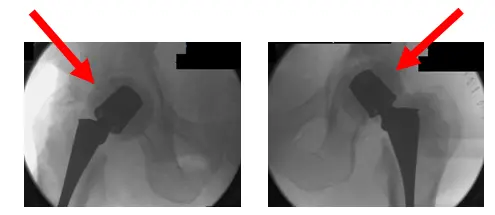

Radiografías intraoperatorias. Las flechas muestran los retractores